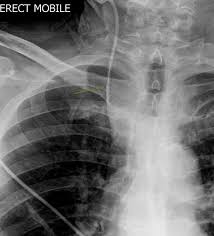

A central venous catheter, also known as a central line, is a tube that doctors place in a large vein in the neck, chest, groin, or arm to give fluids, blood, or medications or to do medical tests quickly. Some catheters have 2 or 3 tubes (called double or triple lumen. Central venous catheter — an intravenous catheter for insertion directly into a large vein, most commonly the subclavian vein. To make the process easier, many pediatric cancer patients have a catheter (a thin, flexible plastic tube) placed under the skin to allow access to a vein. It is acquired by threading a central it is threaded so that the tip of the catheter rests in the lower third of the superior vena cava.

What are central venous catheters? Central venous catheters are helpful for taking care of your child; Indications for central line (central venous catheter) insertion. Central venous catheters(cvcs) are often required to establish venous access in critically ill patients in order to administer rapid fluid resuscitation, blood products, and vasopressors. A central venous catheter is a tube that goes into a vein in your arm or chest and ends at the right side of your heart (right atrium). Central venous catheterization is widely used as a vehicle for rapid volume resuscitation. These are implemented at catheter insertion and for the duration of its use. The internal jugular is usually preferred to subclavian approach where possible as it is less likely to lead to pneumothorax. Internal jugular (ij), subclavian, and femoral. Placement of larger catheters in more centrally located veins is often needed in critically ill patients. However, they can increase the risk of infections when bacteria grow in the catheter and travel to the bloodstream. The physician who is inserting the catheter will make two small incisions on your chest. While cvcs are not considered the best access option and are generally avoided when possible, patients unable to immediately get a fistula or graft, or if their fistula or graft are in the process of healing, may need for a temporary access.

These are implemented at catheter insertion and for the duration of its use. Peripherally inserted central catheters (piccs) and nontunneled central venous catheters (cvcs) are indispensable in current medical practice, with both serving central venous access needs. The pressure monitoring assembly is attached to the. It ends in 1 of the venae cavae just before entering the right atrium. To streamline patient care, our arrow® cvcs are now available with pressure injection capabilities; It is acquired by threading a central it is threaded so that the tip of the catheter rests in the lower third of the superior vena cava. If the catheter is in your chest, sometimes it is attached to a device called a port that will be under your skin. Cancer treatment usually includes a variety of injections, blood draws, and intravenous medications and fluids. A central venous catheter (cvc) is a thin, flexible tube (catheter) that is placed into a large vein above the heart. This is called a central line associated blood stream infection or clabsi. The jugular veins are one of the most popular site. A clabsi can be serious and life threatening. Central venous catheters are helpful for taking care of your child;